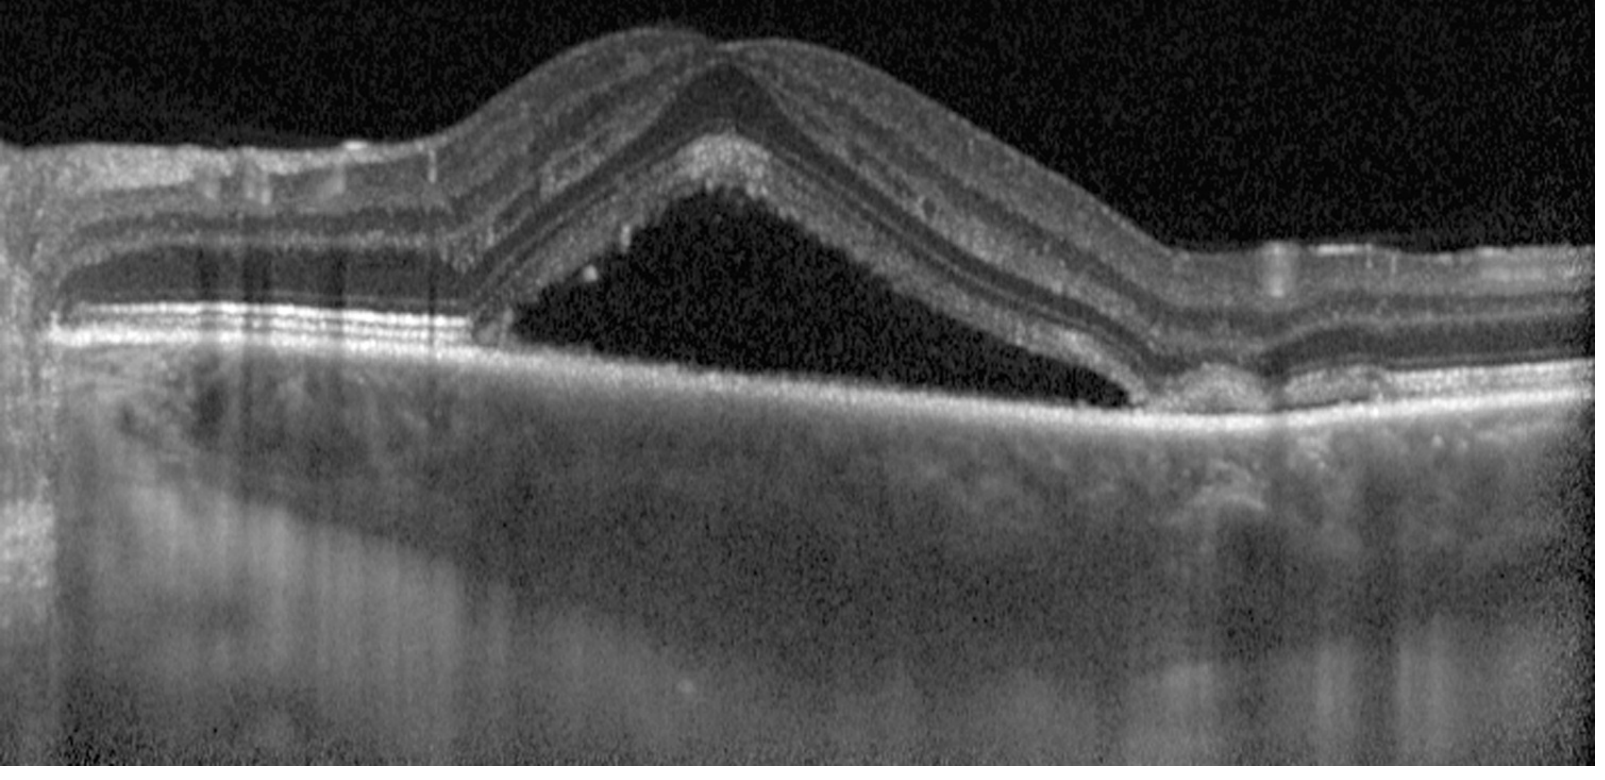

4. OCT (Optical Coherence Tomography) — key investigation; demonstrates subretinal fluid, pigment epithelial detachments (PEDs), and choroidal thickening. Enhanced-depth imaging (EDI-OCT) shows choroidal thickening — a hallmark of pachychoroid disease

EDI-OCT showing subretinal fluid and choroidal thickening in CSCR

EDI-OCT: subretinal fluid pooled under the elevated neurosensory retina with underlying choroidal thickening